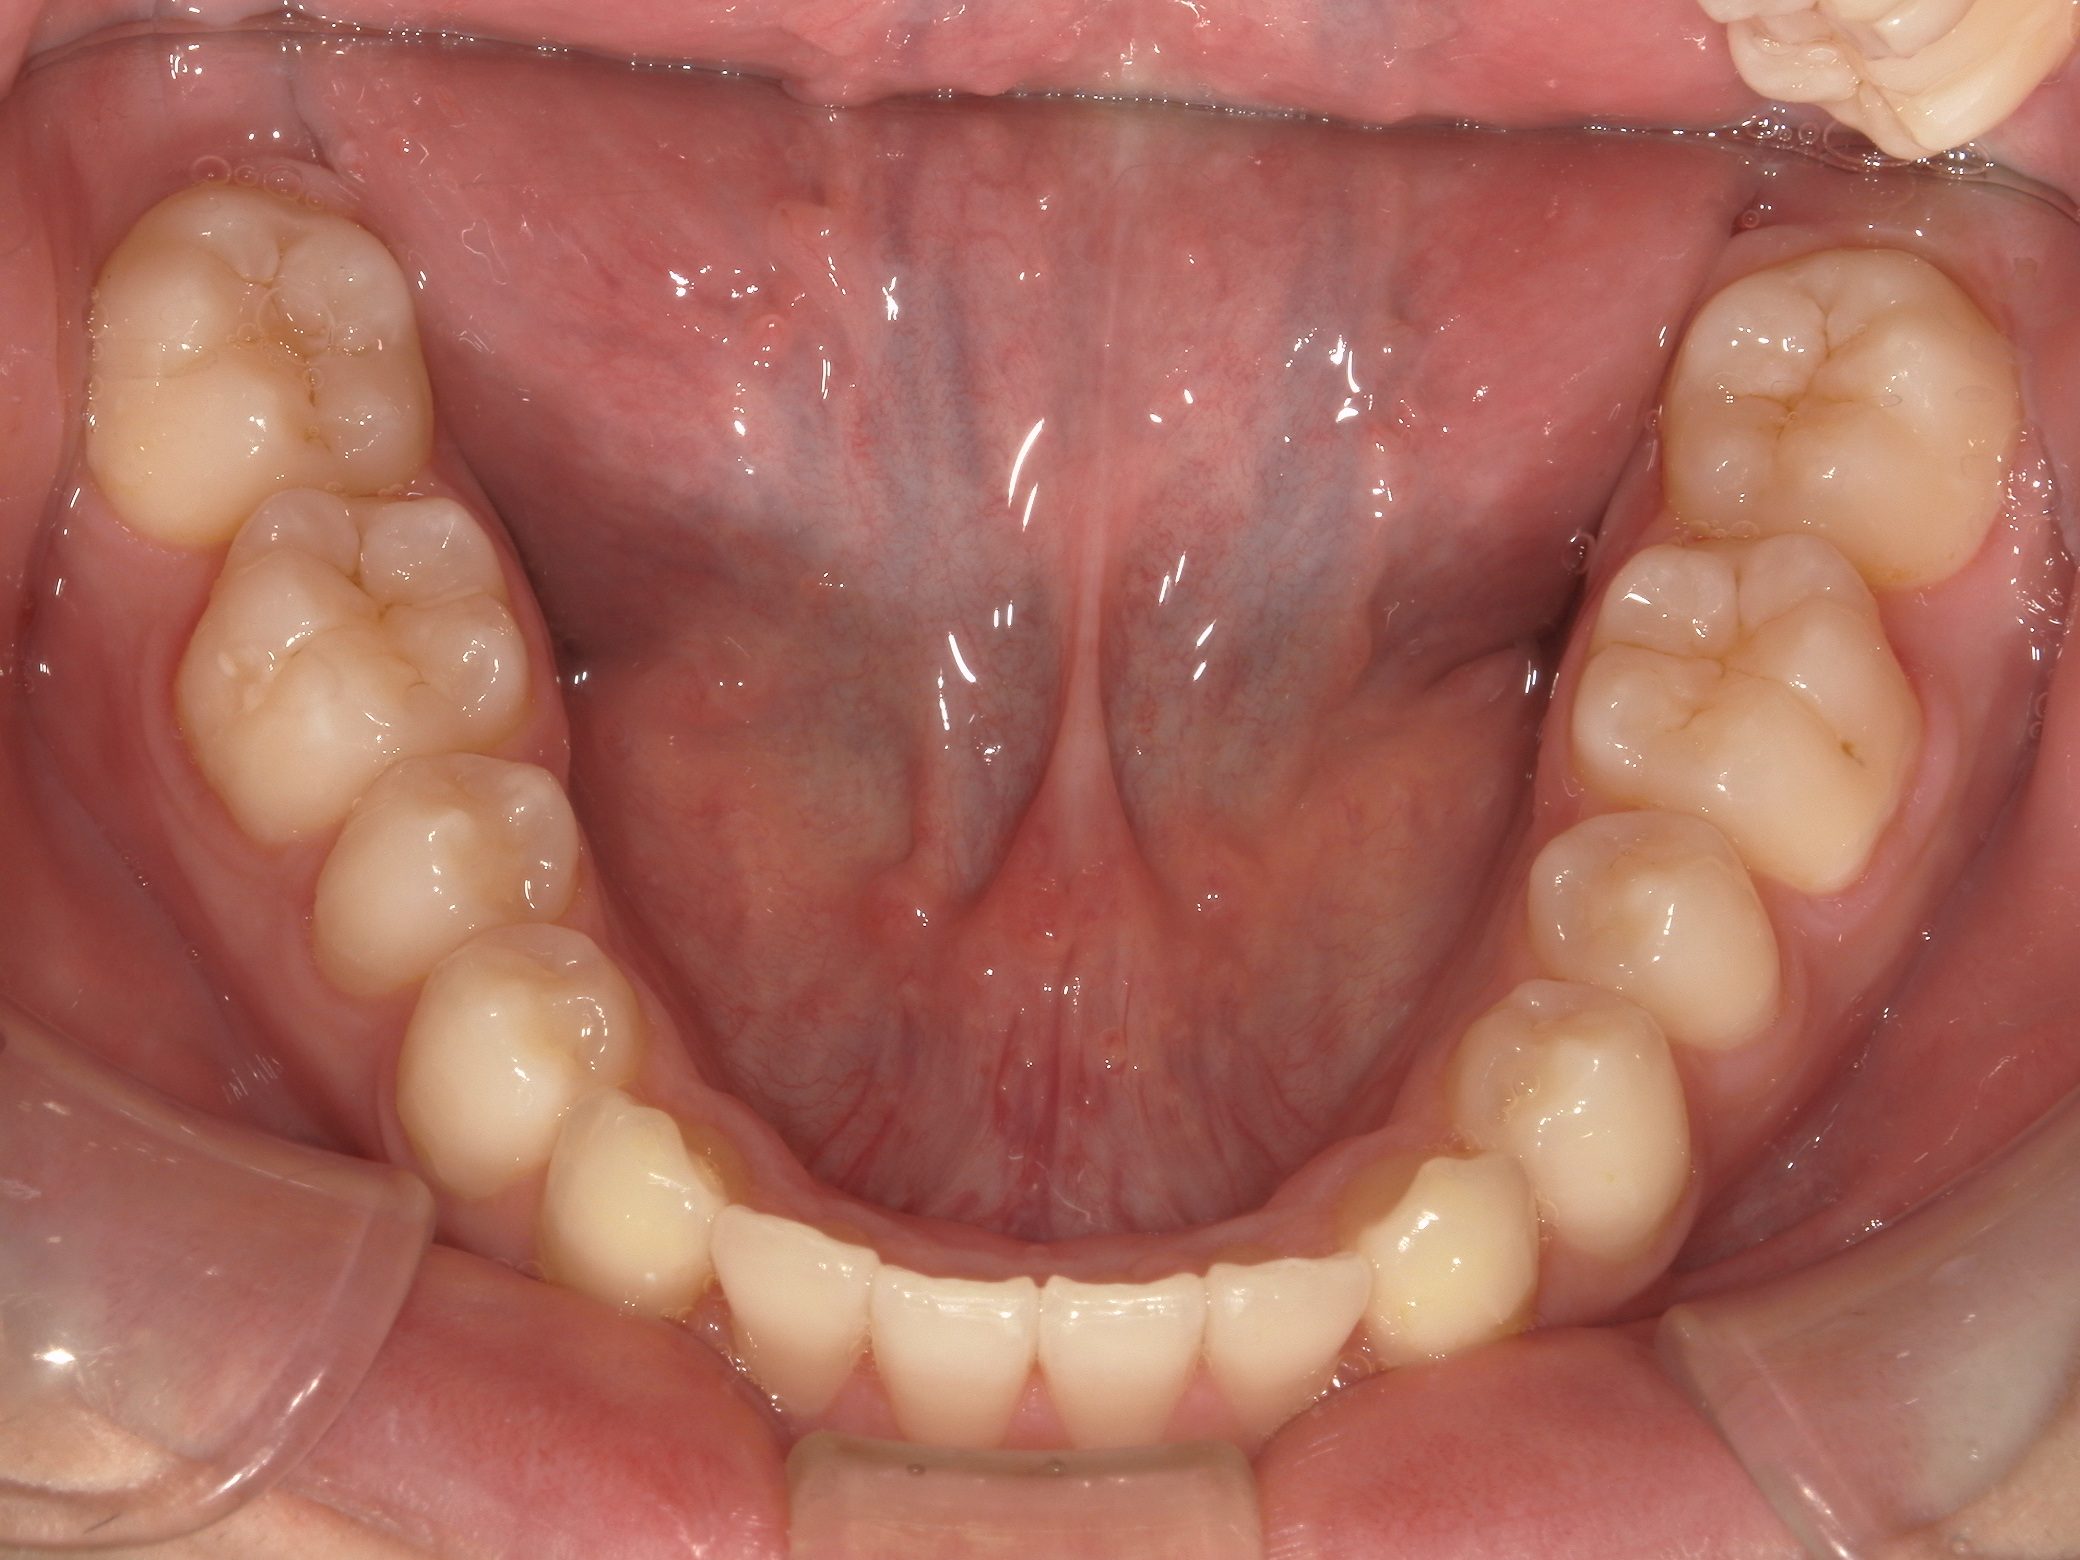

Before

After

治療期間

10か月年

治療開始

19歳

種類

インビザライン矯正

使用装置

インビザラインフル

コメント

すきっ歯なので ディスキングなどもなし

県外の大学に進学されていたので2カ月ごとの来院で10か月で終了

一番奥の歯がすれ違い咬合でしたが、綺麗に治りました。